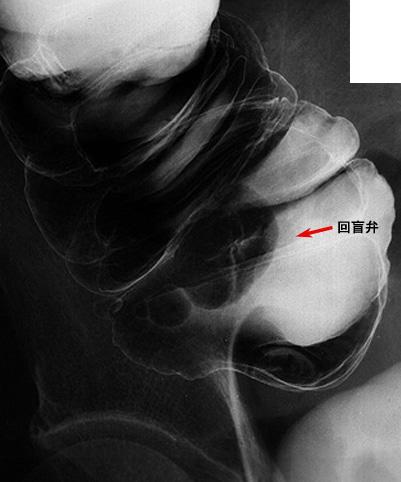

疾病(病理主体)的分类恶性上皮性肿瘤/腺癌

部位(按器官分)大肠/回盲部

检查方法X线

肿瘤的肉眼分类0型(表在型)/IIa型(IIa+IIc)

肿瘤最大直径10~14

肿瘤的深度m